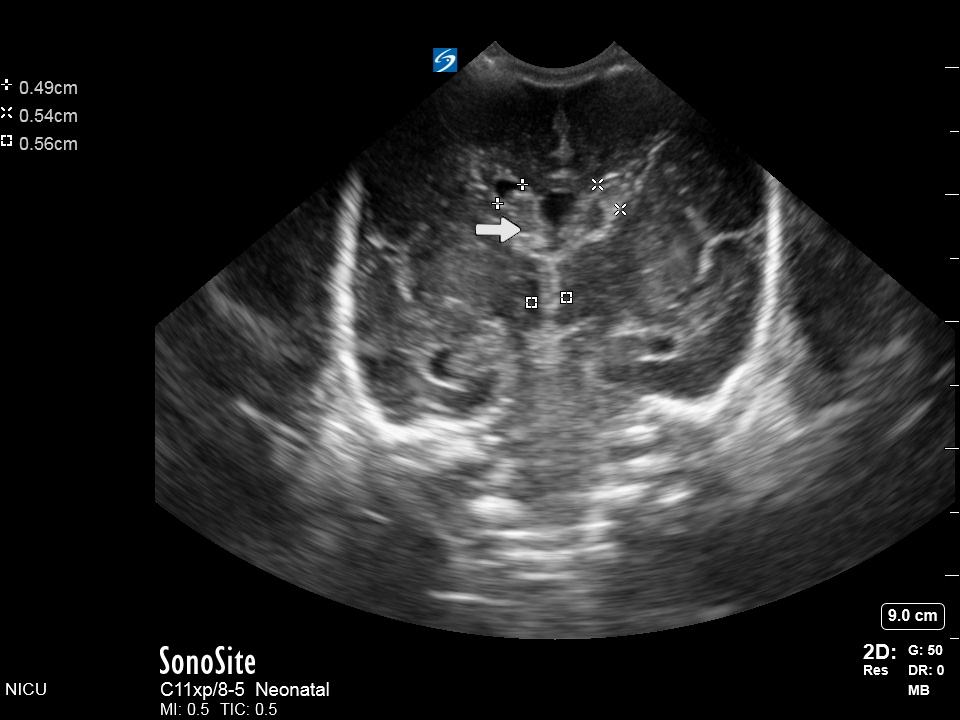

Neonatology Coronal Circle of Willis Image